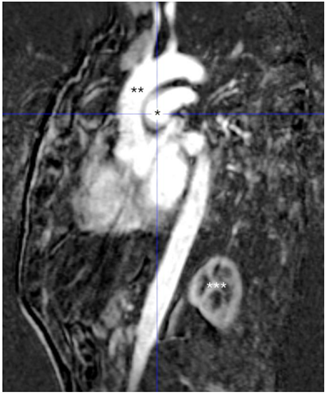

Observe a imagem a seguir.

A RM mostrada acima mostra o seguinte plano e a seguinte provável doença: